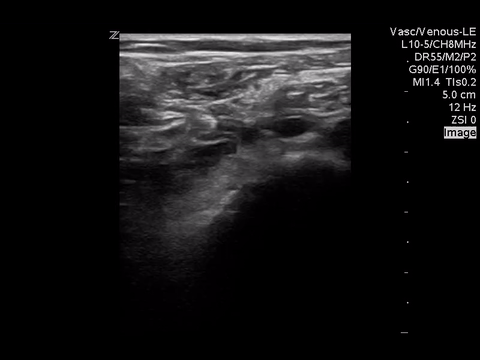

We can eliminate a few diagnoses off the differential with this scan. However, with the diagnosis of PE remaining a 2-point DVT scan was carried out:

Right lower extremity

|

In each of these images it appears the vein fully collapses with compression. We can conclude that there is likely no DVT present within the limitations of the 2-point compression scan (see discussion for further details)